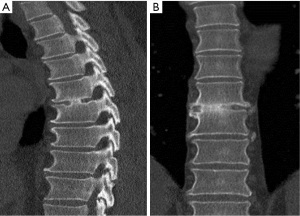

A 49-year-old male presented with a 4-day history of progressive myelopathy with bladder and bowel dysfunction, unsteadiness and leg numbness. He had no medical comorbidities and was a non-smoker. Examination demonstrated spastic gait, positive Romberg’s test, lower limb hyperreflexia with midthoracic sensory level and saddle anesthesia. Thoracolumbar MRI revealed an acute central T6-7 soft central disc prolapse compressing the spinal cord causing intrinsic high cord signal (Figure 1). MRI brain excluded mass lesion and demyelination. Two days of 16 mg dexamethasone treatment was provided without symptom response or improvement. Hence, the patient underwent a right transpleural T6-7 LIF. After complete channel discectomy, a ball tipped hook was used to remove the extruded central disc fragment through a rent in the ruptured posterior longitudinal ligament (PLL). The disc space was distracted with sequential interbody spacer trials until the appropriate height was achieved, followed by cage placement (6×16×35 mm3, 10 degree, CoRoent XL-T). Estimated blood loss (EBL) was less than 50 mL. A postoperative chest tube was not required for drainage. Postoperative chest radiography excluded pneumothorax and CT confirmed cord decompression and satisfactory prosthesis placement at T6-7. The patient exhibited rapid resolution of myelopathic symptoms and was discharged 5 days postoperatively. At 6 weeks postoperative the skin incision was well healed with excellent cosmesis (Figure 2) and he was no longer taking analgesic medication. The patient returned to light work duties at 8 weeks and then to full duties 3 months postoperatively. Solid fusion was confirmed on CT at 6-month follow-up (Figure 3). The patient reported a vast improvement in pain, from a visual analogue scale (VAS) of 10/10 preoperatively, to 1/10 at 24-month follow-up. There were also improvements in Oswestry Disability Index (ODI) (84 to 0), and SF-36 physical component score (PCS) (11 to 50) and mental component score (MCS) (54 to 55).